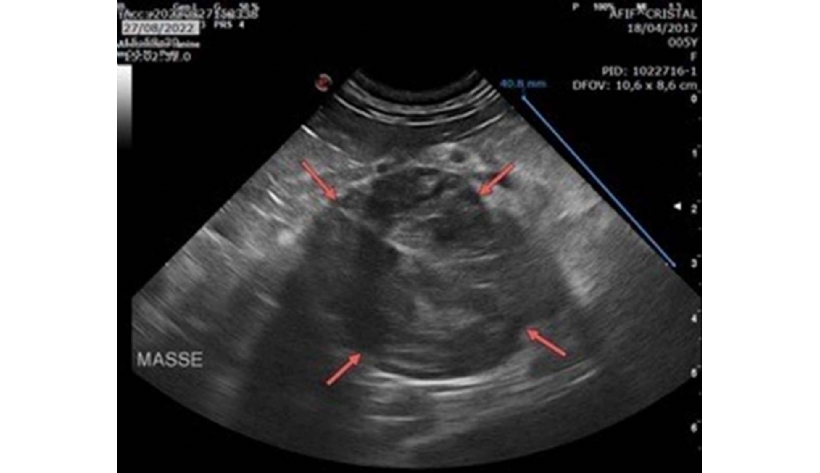

Mercredi 19 Mars 2025 Animaux de compagnieMasse surrénalienne droite de 4 cm de diamètre, d'aspect hétérogène (flèches rouges).

© D.R.